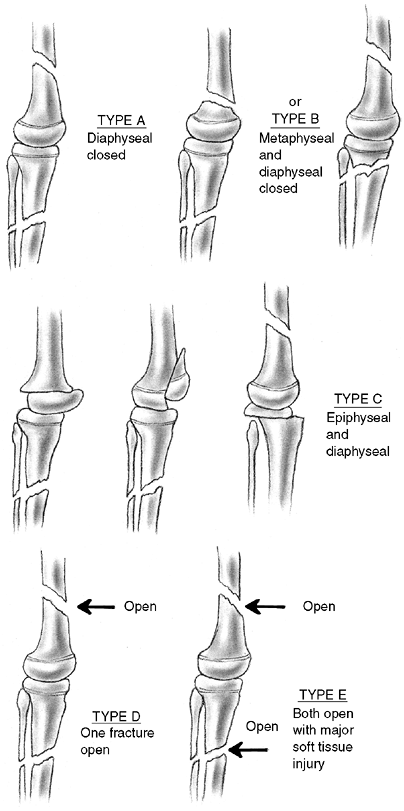

![]() |

|

Figure 33.4 Growth arrest patterns. A: Type I is peripheral growth arrest with a peripheral bony bar. B: Type II is central growth arrest with central physeal tethering. The peripheral physis and perichondrial ring are intact. C:

Type III is combined growth arrest, demonstrating a linear bar involving the peripheral and central portions of the physeal plate. This type of growth arrest is more typical after a Salter-Harris type III or IV fracture. |